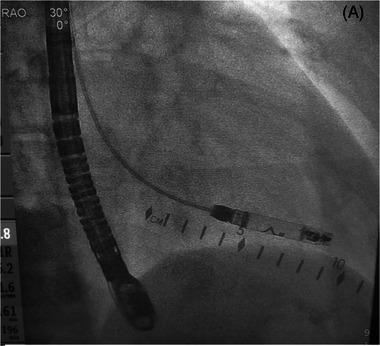

Dual Chamber Aveir Retrievable Leadless Pacemaker Implant via the Right Internal Jugular Vein in a 13-Year-Old With Congenital Complete Heart Block.

Introduction: Congenital complete heart block is a condition where there is a risk of Stokes Adam's attacks and sudden death may occur. Once the escape rate is too low, or other high-risk factors occur, these patients ultimately need pacemakers placed. Epicardial or transvenous pacemakers have typically been in employed dependent on size of the patient and other circumstances. We describe the first case of an implant via internal jugular vein (right) of a dual chamber leadless pacemaker implant in a symptomatic pediatric patient with congenital complete heart block.

Case: A 13-year-old presented with presyncope at rest after years of being followed for her congenital complete heart block. Her average rate on Holter monitoring was below 50 bpm, which coincided with her recent symptoms. After discussion with family, and our own cardiology/surgical team, she had a dual chamber leadless pacemaker implanted. Stable 3-month atrial parameters included an impedance of 340 Ω, sensing of 3.2 mV, and threshold of 0.25 V at 0.2 ms, while ventricular parameters showed an impedance of 780 Ω, sensing of 14.2  mV, and threshold of 0.5 V at 0.2 ms.

Conclusion: Dual chamber leadless pacemaker implant is feasible via right internal jugular vein access and in a pediatric patient.